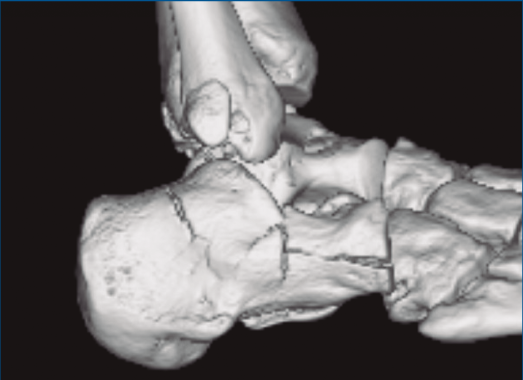

Figura 2. Fractura maléolo peroneo y tibial posterior. Trazo entre fragmento anteromedial y posterolateral.

Figura 3. Desplazamiento entre fragmento anteromedial (sustentaculum tali) y posterolateral (tuberosidad).

Se trata de un varón de 19 años que ingresa en reanimación tras precipitarse desde una altura de aproximadamente 10 metros. El paciente presenta una fractura estallido de L3 con afectación del canal medular junto con una fractura del vértice inferior de L4, así como una fractura luxación de calcáneo, asociada a una fractura del maléolo peroneo y del maléolo tibial posterior (Figuras 1 a 6) diagnosticadas mediante TC total body (por eso no se dispone de radiografías simples al momento del ingreso). Como podemos comprobar, se trata de una fractura de doble trazo de tipo hundimiento/depresión de la carilla articular (Figuras 5 y 6).

Figura 5. Fractura maléolo peroneo, luxación astrágalo, fractura de doble trazo en calcáneo.

Figura 6. Fractura de doble trazo; se evidencia afectación de la articulación calcaneocuboidea.